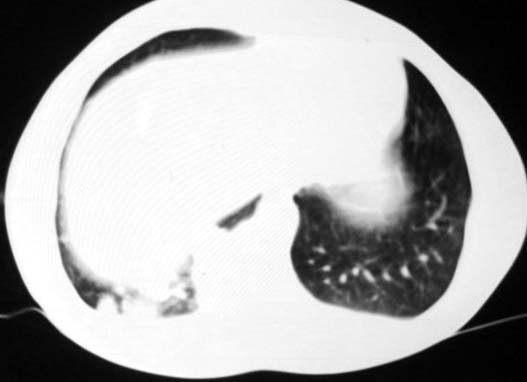

标题: CT5614:外伤病人男,20岁,右上腹痛.余肺野(-) [打印本页]

标题: CT5614:外伤病人男,20岁,右上腹痛.余肺野(-)

其次,病灶较多并散布在右下肺底,纵肺比例明显小于50%,与膈肌以及后壁胸膜有轻度粘连。且其内密度不均匀,最大的那个结节影里面有较致密密度,胸椎旁似乎还有液平面。也就是说右下肺炎性改变可以肯定。

外伤病人男,20岁,右上腹痛,ct显示:右肺下叶后基地段见斑片状高密度影,密度不均,边界清,考虑1,右肺下叶肺挫伤;2,炎症。

可以肯定的是与外伤无关。肺挫伤是片状渗出影:边缘比中心密度低,呈毛玻璃状,如果是结节状肺挫伤(肺内血肿)应该边缘光滑,不会与后壁胸膜有轻度粘连。此病灶分叶状,周围有卫星灶(纤维条索影及小结结影),考虑结核.